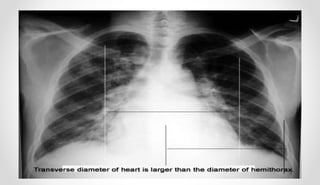

• Chest X-ray- Cardiomegaly

DIAGNOSIS • Major andminor critera • Echocardiogram- valvular insufficiency pericardial fluid/thickening • Chest X-ray- Cardiomegaly • ECG- AV conduction delay